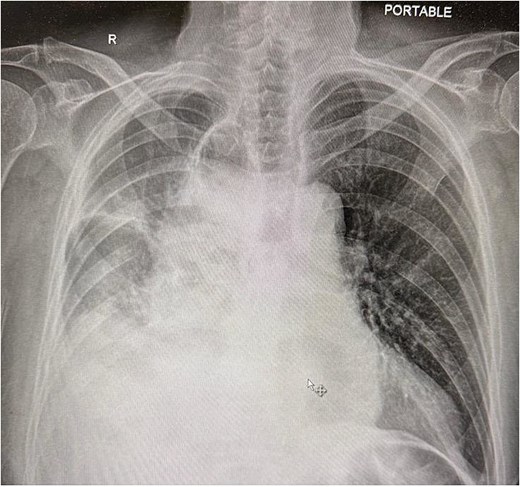

Upon arrival at the ED, the patient was afebrile and hemodynamically stable. Initial labs showed WBC 10.19, H/H 13.2/41.3, platelets 419, Na 136, K 5.3, creatinine 1.0. Portable X-ray and computed tomography (CT) imaging revealed small bowel obstruction secondary to herniation of the small bowel into the right hemithorax through a recurrent hiatal hernia (Figs 1 and 2).

Chest X-ray showing compressed lung and fluid due to herniated small bowel.